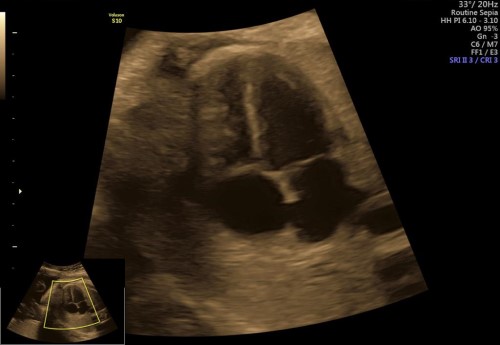

Realizamos ultrasonidos fetal avanzado desde el primer trimestre como el USG genético, USG estructural (sem 18-22) y estudios de bienestar fetal con tecnología Doppler para medición de flujos sanguíneos fetales como arteria umbilical, cerebral media, ductus venoso y en la madre las arterias uterinas.